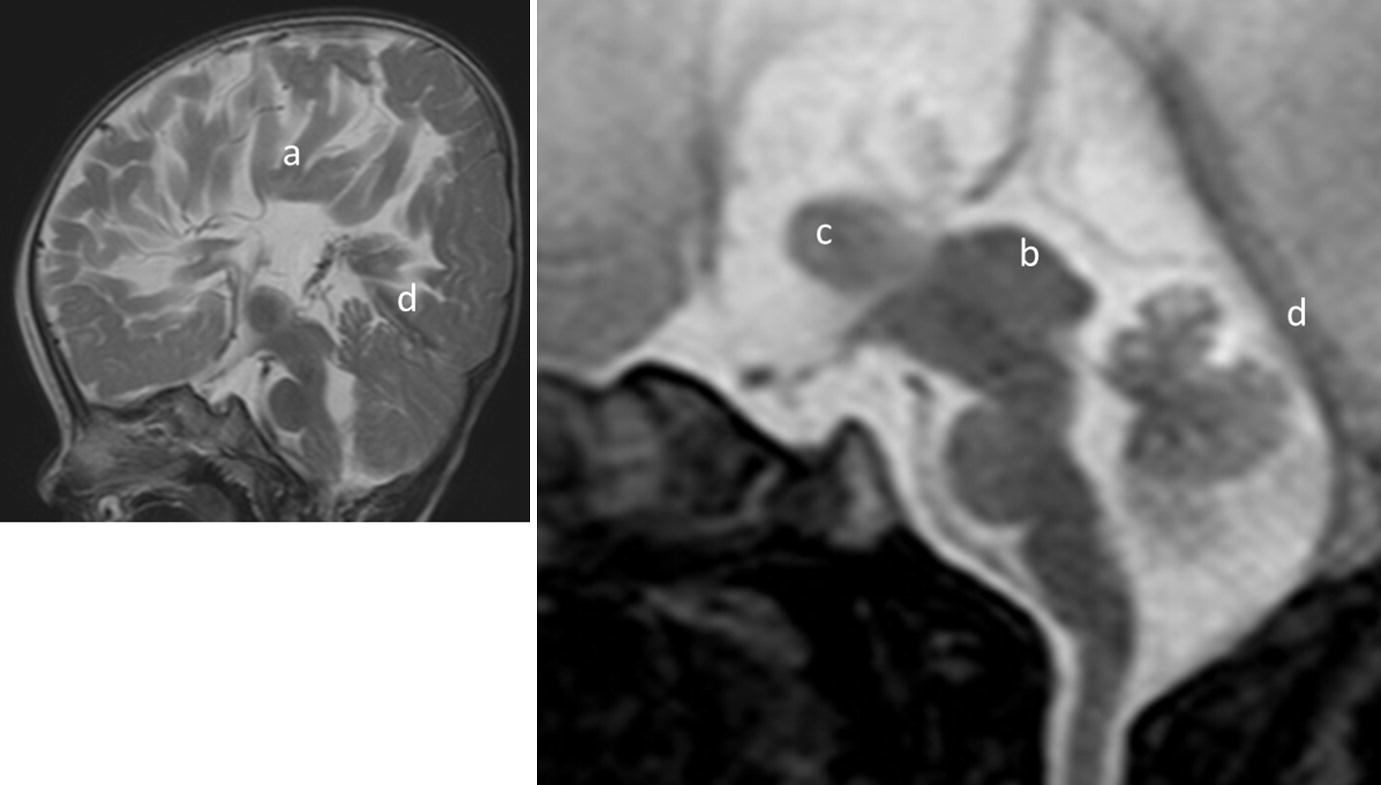

masa syndrome in twin brothers

pdf masa syndrome new clinical

l1 syndrome genereviews ncbi bookshelf

x linked hydrocephalus springerlink

masa syndrome wikipedia